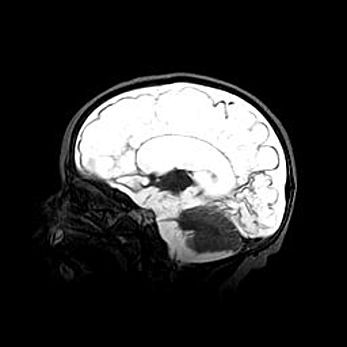

Мальформация Денди-Уокера. Киста задней черепной ямки.

Агенезия мозолистого тела.

Возраст: 2,5 месяца

Вес: 2420 г

Пол: женский

Окружность головы: 37 см

Срок гестации: 32 недели

Мальформация Денди—Уокера — редкий вид патологии ЦНС, представляющий собой врожденный порок развития каудального отдела ствола и червя мозжечка, ведущий к неполному раскрытию срединной (Мажанди) и латеральных (Лушка) апертур IV желудочка мозга. Для этогно синдрома характерна триада симптомов: гипотрофия червя мозжечка и/или полушарий мозжечка, кисты задней черепной ямки, гидроцефалия различной степени. В 70% случаев порок сочетается и с другими аномалиями головного мозга, в частности с агенезией мозолистого тела.